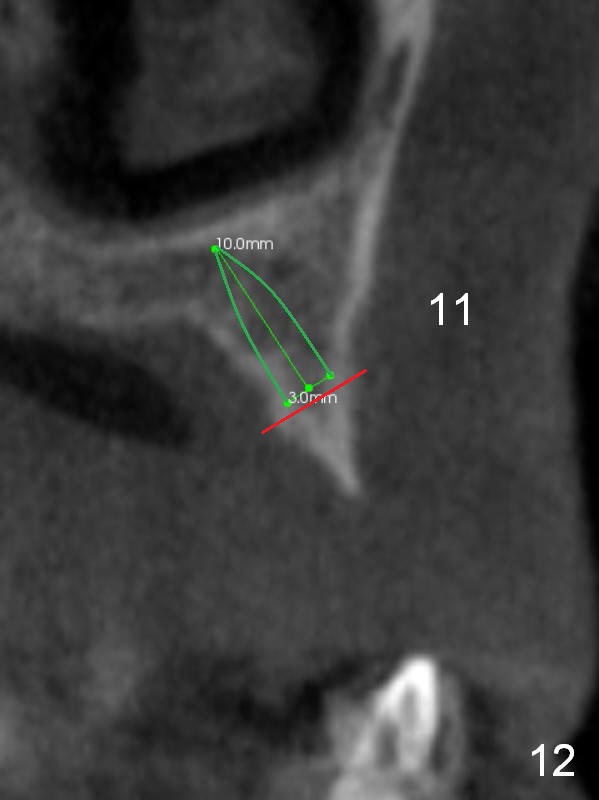

The ridge at #11 is similar to that at #10 (Fig.10), the treatment modality is the same (Fig.11,12). Comparison of the last 2 figures show that implant placement parallel to the palatal wall results in better trajectory for restoration.